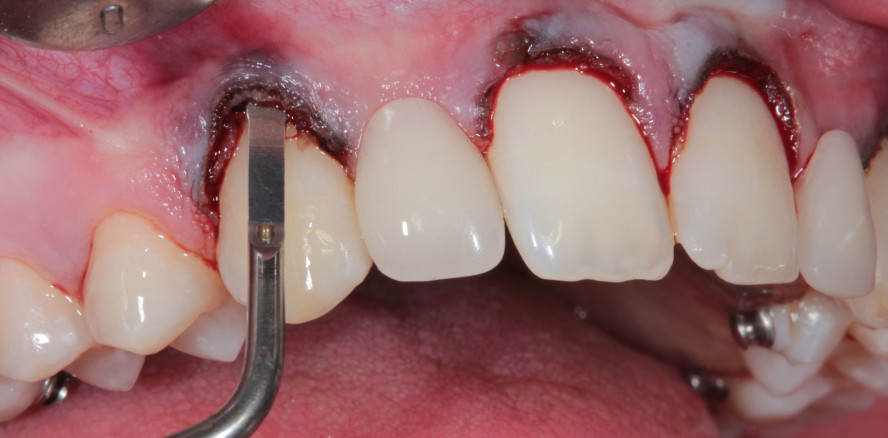

Schwenk und Striegel entwickelten eine Methode zur internen Osteotomie ohne Lappenbildung unter Verwendung einer am Außenrand diamantierten Schallspitze (SFS120).

Man kann sich das Schallinstrument wie eine abgeflachte Kugel vorstellen, die sowohl zum Zahn als auch zur Gingiva hin glatt poliert ist und nur am dünnen krestalen Ende diamantiert. Das erzeugt eine sehr effektive knöcherne Reduzierung. Eine kontrollierte Osteoplastik kann am bukkalen Knochen vorgenommen werden, ohne die Weichteile dabei zu traumatisieren. SFS120 wurde für die Knochenbearbeitung im Frontzahnbereich konzipiert, die um 90° gedrehten Varianten SFS121 und SFS122 für den Approximalbereich. Sie finden ihren praktischen Einsatz besonders bei Kronenversorgungen im Seitenbereich, wo der Kronenrand oft zu nah am Knochen ist. Risiken wie eine Rezessions- oder Narbenbildung sind mit ihnen ausgeschlossen.

Nach Messung der biologischen Breite erfolgt die Planung mittels Mock-up, Wax-up oder Schablone. Für den eigentlichen Eingriff wird der geplante Verlauf mit wasserfestem Filzstift direkt auf die Gingiva gezeichnet. Nach der Gingivakorrektur wird die Osteotomie durch leichtes Schwenken der Schallspitze nach mesial und distal vorgenommen. Um keine Stufen entstehen zu lassen, muss der Behandler lernen, zu differenzieren, wann er die Maßnahme durch den Parodontalspalt vornehmen kann oder wann er tatsächlich aufklappen muss. Auch ist darauf zu achten, den Knochen erst auszudünnen, bevor er reduziert wird, ansonsten werden die Stufen wulstig.